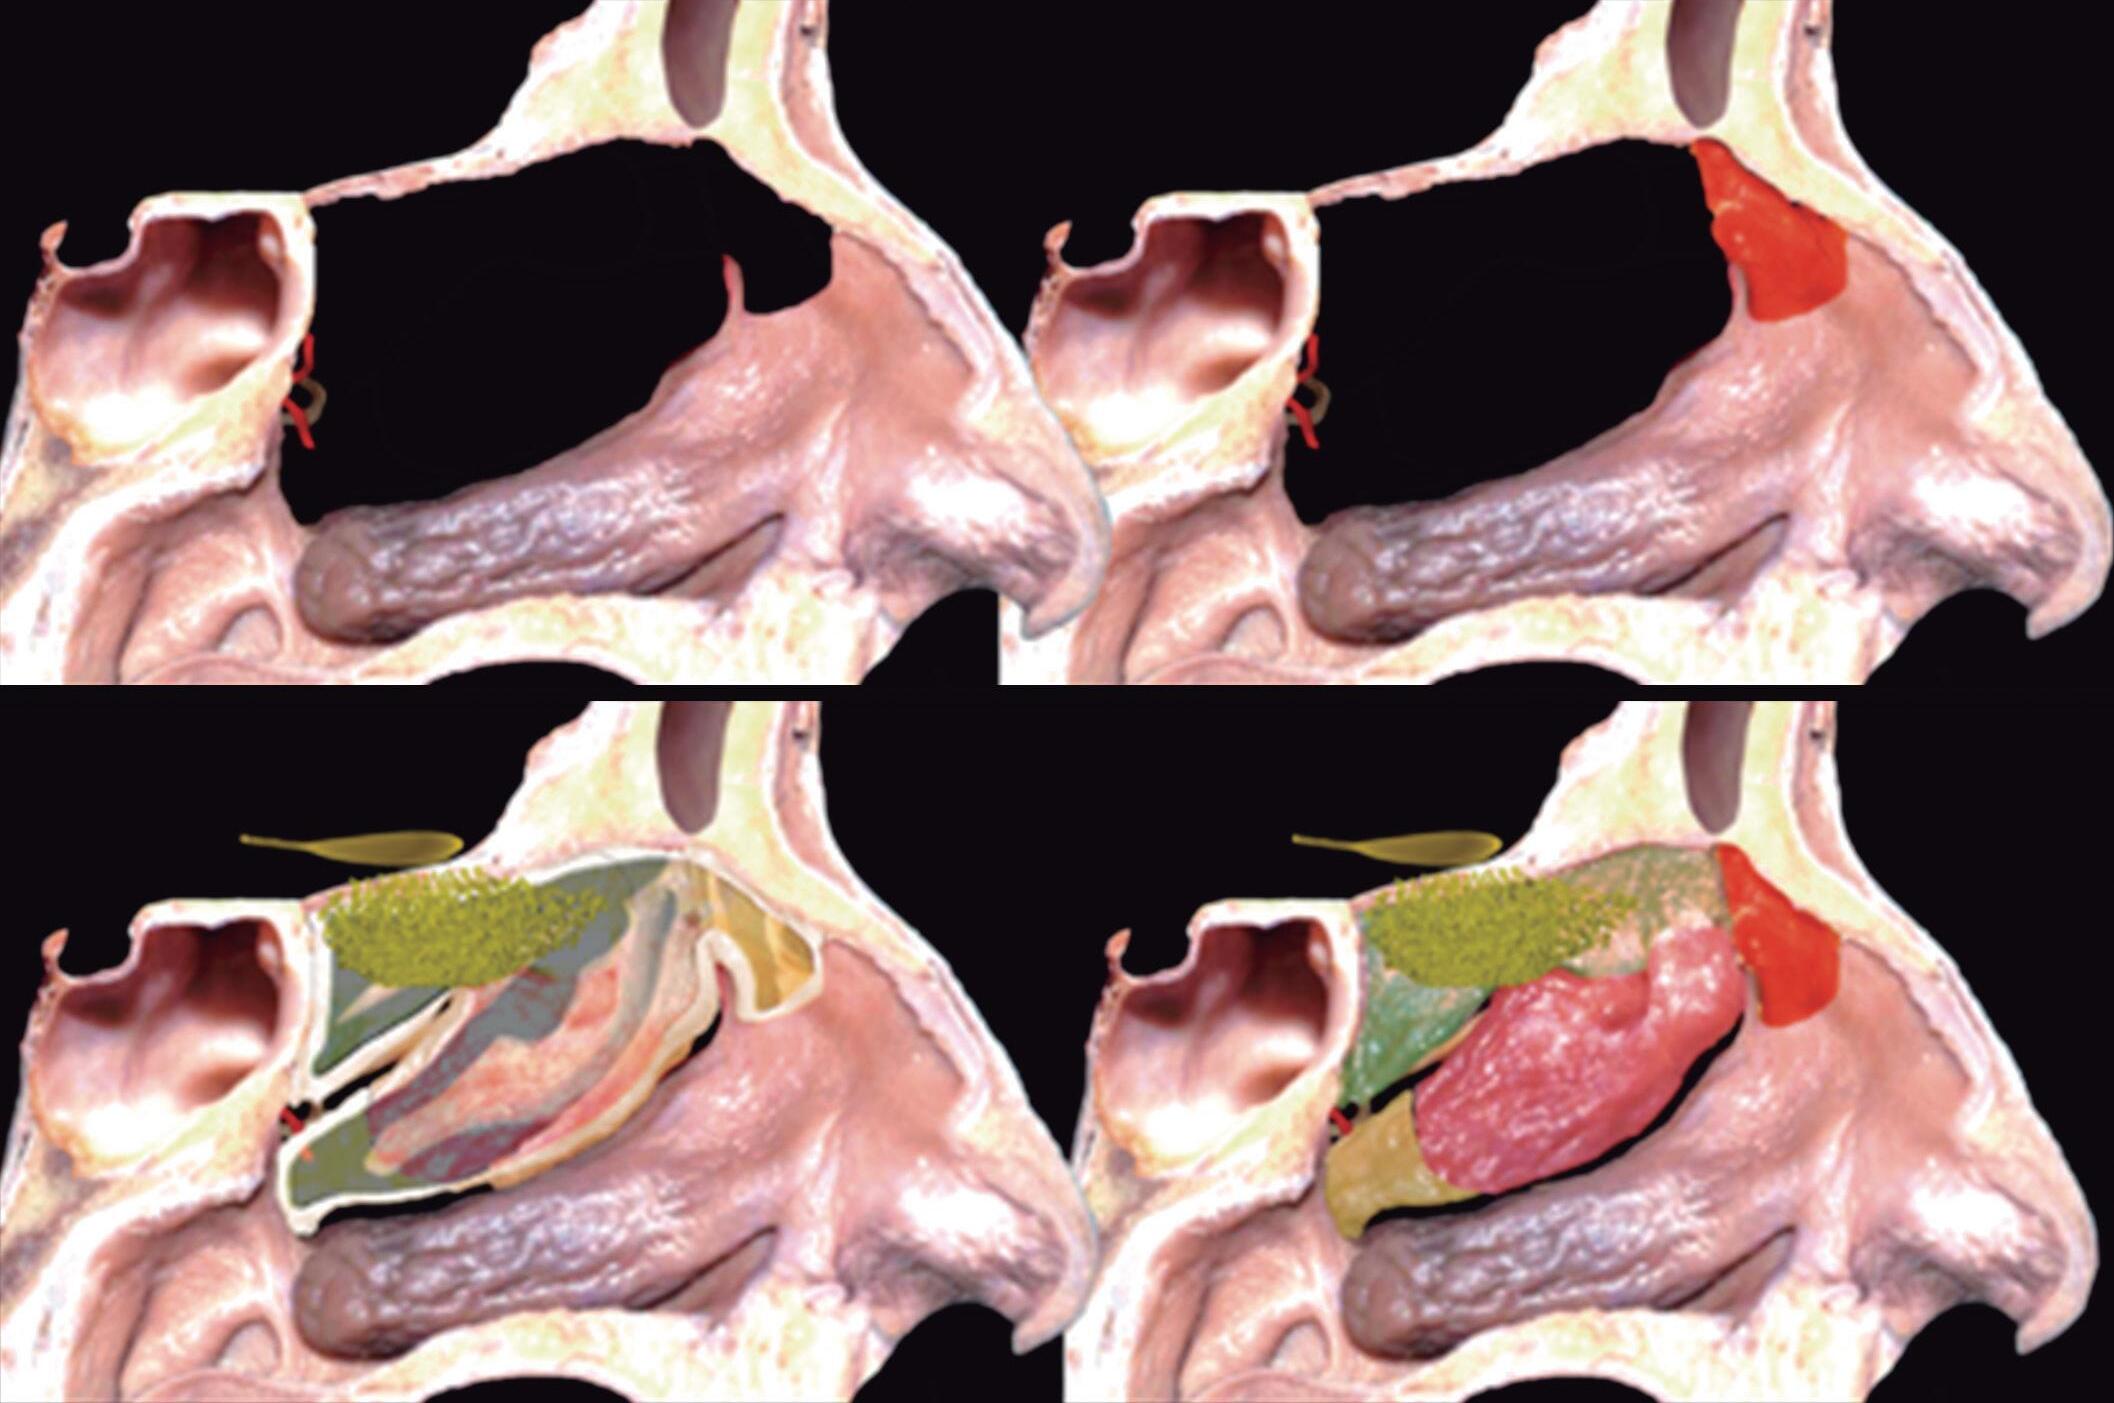

1-4. TC e reconstrução 3D com destaque para estrutura etmoidal (em vermelho), funcionando como câmaras de baixa pressão para drenagem do seio maxilar.

1-7. TC com reconstrução 3D mostrando em vermelho apenas o seio etmoidal e não o osso etmoidal, e sua relação com a fossa nasal, o seio maxilar, órbita e fossa anterior.

1-8. Osso etmoidal e seio etmoidal (amarelo) observar o aspecto incompleto do teto do seio etmoidal que será coberto pelo osso frontal (rosa).

Este complexo anatômico chamado seio etmoidal, controla a pressão e o fluxo aéreo que penetra nos verdadeiros seios paranasais e pode ser interpretado como um sistema de câmaras aerodinâmicas de baixa pressão cuja topografia particular faz dele o centro anatomofuncional do aparelho rinossinusal.

Fig. 1-45. Limites do seio etmoidal: (1) Limite anterior: junção da placa do agger nasi com o processo frontal do maxilar; (2) limite posterior: parede anterior do seio esfenoidal; (3) limite lateral: processo frontal do maxilar mais anteriormente, osso lacrimal (unguis) e a parede medial da orbita (lâmina papirácea) posteriormente; (4) limite superior: piso da fossa anterior, composto anteriormente pela parte medial do processo orbital do osso frontal e posteriormente pelo plano esfenoidal; (5) limite medial: estrutura vertical da concha média; (6) limite inferior: o seio etmoidal comunica-se livremente com a fossa nasal.